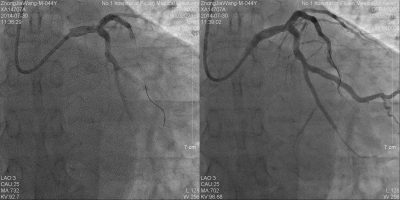

造影结果(二):

![]()

造影结论及应对策略:本病例行冠脉造影发现: 右冠优势型,LM末端斑块溃疡、LAD、D未见明显狭窄,mLCX约95%狭窄,OM无明显狭窄,TIMI血流3级,见回旋支到右冠侧枝循环。mRCA闭塞。造影后向患者家属交代病情,与家属沟通后决定做介入治疗。